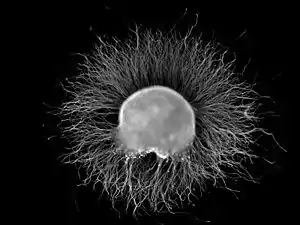

A dorsal root ganglion (DRG) from a chicken embryo (around stage of day 7) after incubation overnight in NGF growth medium stained with anti-neurofilament antibody. Neurites growing out of the ganglion are visible. | |